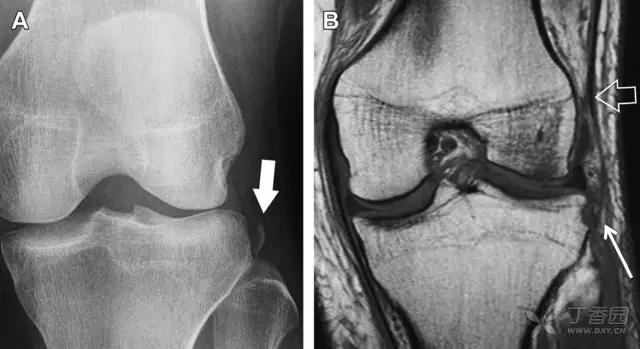

10 胫骨后外侧碎片骨折

胫骨后外侧小片骨皮质的压缩性骨折,可能是旋转移位损伤的唯一证据(图 3)。这种骨折在常规膝关节平片很难发现,若怀疑存在骨折,行下肢内旋斜位片检查可诊断。

图 3 胫骨后外侧碎片骨折

A 正位片示胫骨后外侧处可见一压缩骨折的小碎片(方框)。这是胫骨撞击股骨外侧髁旋转移位时所致。B 另一位患者的 MRI 矢状位 T1 加权像示胫骨后外侧骨折碎片(箭头)。